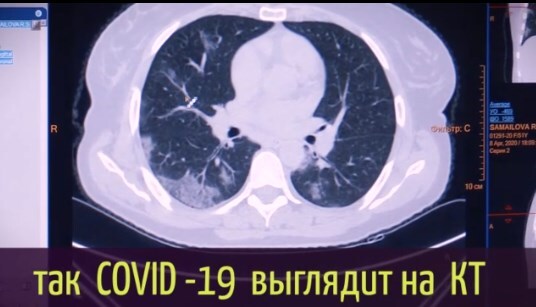

Японские и американские врачи обнаружили патологию у людей, которые переболели коронавирусом без симптомов.

У некоторых пациентов происходят изменения в легких.

Отмечается, что человек чувствует себя нормально, но коронавирус повреждает легочную ткань, на которой образуются уплотнения.

Врач-рентгенолог "Медико-хирургического центра на Пресне" Людмила Леонова пояснила, что воспаленная зона в легких начинает фиброзироваться (фиброз – уплотнение легочной ткани).

По ее словам, если болезнь протекает в легкой форме, то фиброз со временем проходит. Однако в тяжелой форме он чаще всего остается, учитывая возрастные показатели населения.